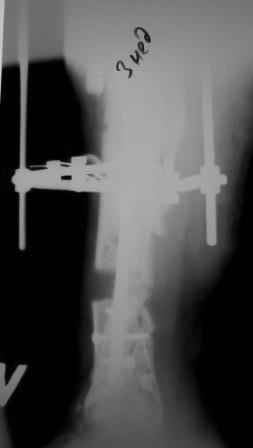

Коллеги!Позвольте продолжить обсуждение темы «ложный сустав левой голени.» Больной К 45 лет, начало см. http://www.weborto.net/forum/1228422607/ И рассказать о результатах проделанной работы. Остановились на следующей тактике 1) Наложить Аппарат Илизарова. В аппарате восстановить оси трех смещенных относительно друг-друга фрагментов большеберцовой кости. Устранить вальгусную деформацию дистального отдела большеберцовой кости. Что и было выполнено. - Была выполнена репозиция в аппарате (рис1) 2) После репозиции более очевидна стала проблема дефекта кости в верхней трети голени, два фрагмента свободно лежат. Остановились на варианте перехода на интрамедуллярный синтез стержнем с покрытием костный цемент+ванкомимцин и замещении дефекта с помощью транспорта фрагмента (рис 2) 3) Третьим этапом наложили модуль на промежуточный фрагмент.(рис 3) И начали его транспорт на стержне в проксимальном направлении. (рис 3 а) Надеемся что «вырастет» регенерат в дистальном отделе, а в проксимальном отделе фрагмент «упрется» и прирастет. Хочу сказать слова благодарности за обсуждение на форуме этого случая. Особые слова благодарности Иванову Павлу Анатольевичу!!! Он помогал Словом, а самое главное делом. Приезжал, оперировал! За что ему нижайший поклон! С ув Коробушкин Г

Меня расстраивает значительное вальгусное смещение проксимального отломка большеберцовой кости. Оно очень значительное. Рассверливание

костно-мозгового канала во время операции было непростым, и за время его проведения канал в проксимальном отломке образовался избыточным по

диаметру. Это в определенной мере способствовало образованию данного смещения. Жаль, что в конце операции мы недооценили его степень, иначе

бы устранили его при помощи винта-поллера. Может быть, участники Ортофорума что-либо посоветуют по этому поводу. Стоит ли как-то попытаться исправить ситуацию?